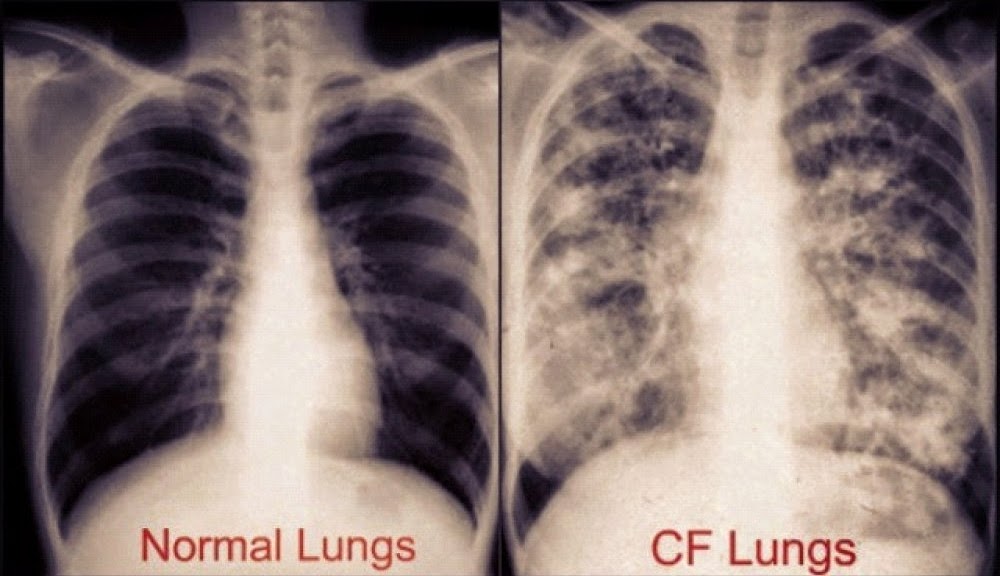

Πώς φαίνεται η κυστική ίνωση (Cystic Fibrosis – CF) στην ακτινογραφία